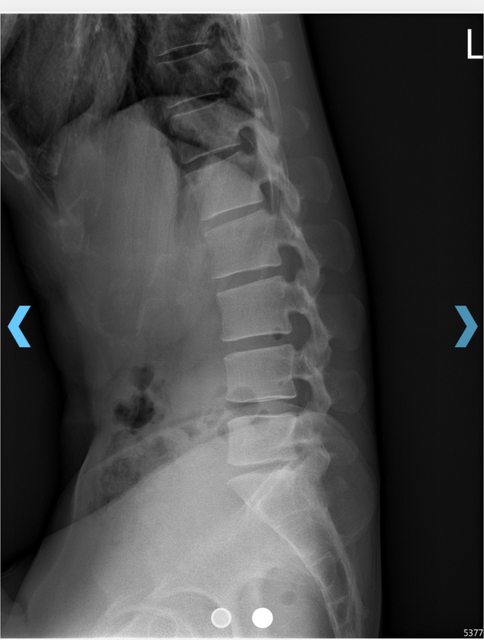

馬偕醫院拍的X光片 https://i.imgur.com/GEgkCA4.jpeg

juor2: 但你的X光我有講了就慢性退化的椎間盤突出跟我本人一樣 06/06 21:56

juor2: 但說實話你的X光用間接證據看,椎間盤突出或是退化是機率06/06 23:30

juor2: 很高,會建議先讓急性期下來。當時不確定你會想要自費作治 06/06 23:31